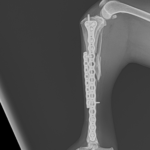

13歳のトイ・プードルがソファーからジャンプした際に後肢を傷めて救急病院を受診されました。エックス線検査で脛骨近位部の粉砕骨折(comminuted tibial fracture)が確定され、骨固定術の依頼がありました。小型犬では、ソファーやベッドなどの高さからのジャンプでも骨折が起こることがあります。特に高齢になると、骨密度の低下、骨皮質の菲薄化などにより、比較的弱い外力でも骨折が起きやすくなるため注意が必要です。今回の患者さんではOrthogonal ロッキングプレート固定+髄内釘(Plate–Rod construct)により骨折部を安定化しました。粉砕骨折では骨片を無理に整復せず、生物学的固定(biologic fixation)により自然な骨癒合を促す方法が現在の主流です。高齢犬でも適切な固定を行えば、良好な骨癒合と歩行回復が期待できます。